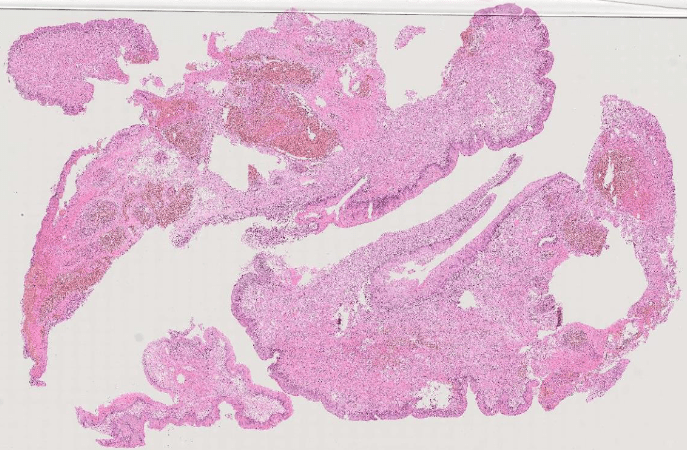

lung adenocarcinoma

colon cancer

endometrial cancer